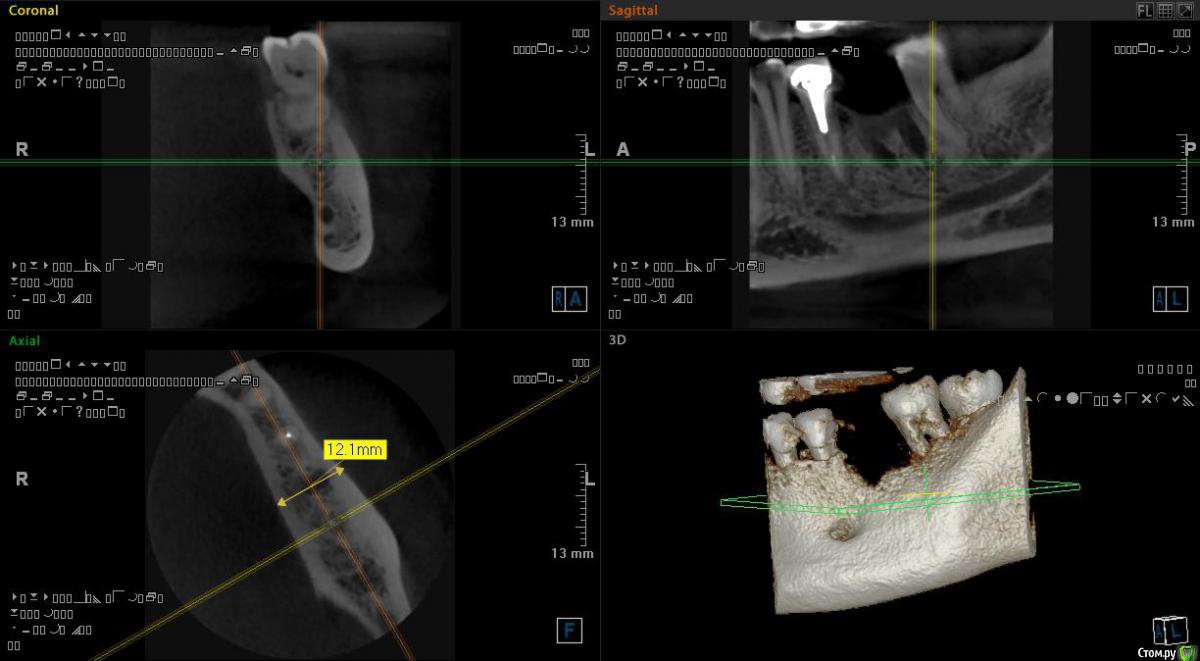

Самарец Опубликовано 11 августа, 2020 Поделиться Опубликовано 11 августа, 2020 (изменено) Добрый день!4 месяца назад удалена нижняя 6-ка под последующую имплантацию. Операция и заживление прошли отлично. Вчера сделал КТ и расстроился. По снимку - как- будто удаление прошло вчера....Скажите пожалуйста возможна ли имплантация?Заранее благодарю! Изменено 11 августа, 2020 пользователем Самарец Ссылка на комментарий

red_butler Опубликовано 11 августа, 2020 Поделиться Опубликовано 11 августа, 2020 срезы выставлены не корректно, покажите еще, в том числе в области седьмого зуба Ссылка на комментарий